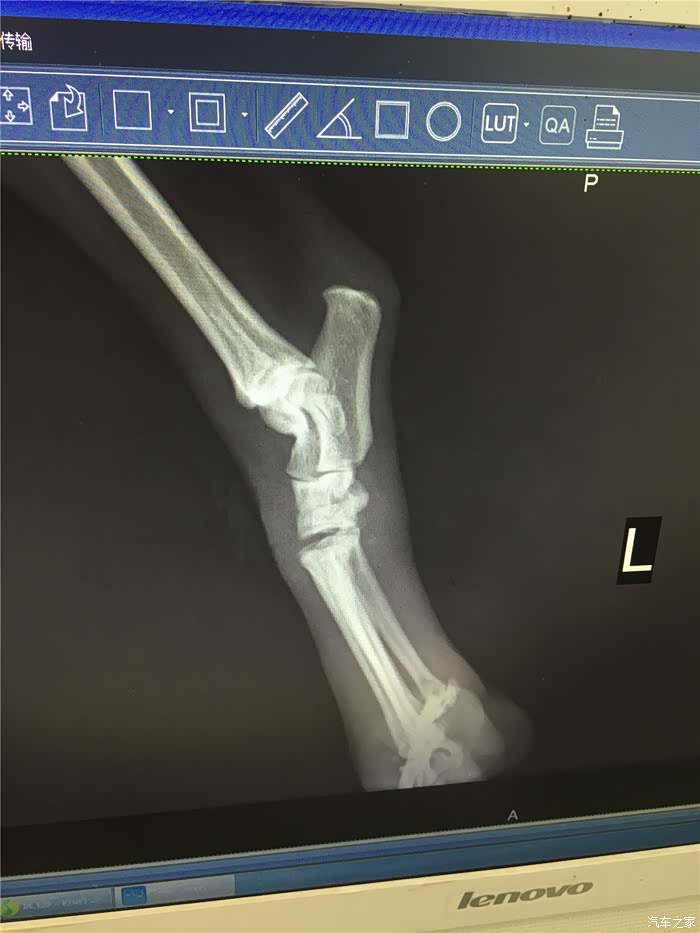

回拉萨途中,dido妈已经告诉我,他们找到了一家宠物医院,是拉萨警犬指定医院,有dr设备,据说比X光更好

上海的医生朋友也说,dr设备还是比较先进的,看的比较清楚

拍片。果然是骨折了,但是并不算严重,骨头甚至没有完全断开。

医生建议外部固定,静养恢复。

询问了上海的宠物医生,把dr图拍下给他看过,也说可以外部固定。